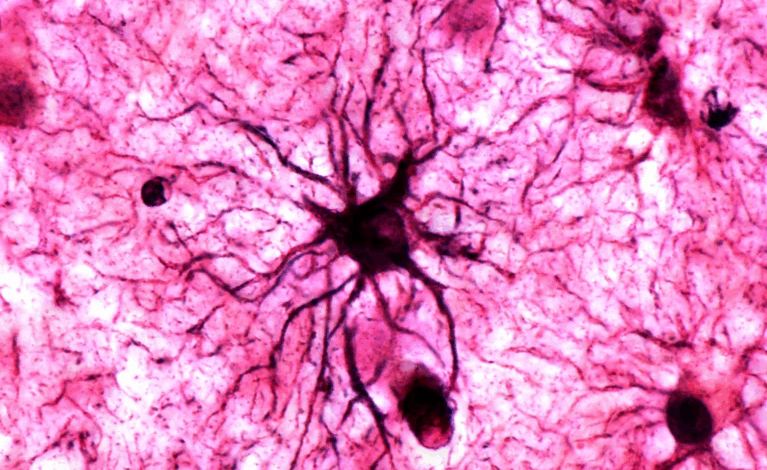

Descoberta revela papel dos astrócitos na formação de memórias emocionais

Um estudo publicado na revista Nature trouxe novas evidências sobre como o cérebro armazena lembranças marcadas por emoção. Pesquisadores do Centro RIKEN de Ciência do Cérebro, no Japão, identificaram que os astrócitos — células até então vistas apenas como coadjuvantes dos neurônios — têm papel fundamental na estabilização de memórias de longo prazo, especialmente as associadas a experiências emocionais intensas. A descoberta pode abrir caminho para novas terapias contra doenças como Alzheimer e transtorno de estresse pós-traumático (TEPT).

A análise genética revelou ainda que os astrócitos ativos produzem receptores noradrenérgicos, proteínas que respondem à noradrenalina, substância responsável por ativar essas células e fortalecer sua comunicação com os neurônios. Segundo os autores, essa resposta prolongada permite que as memórias emocionais sejam transformadas em traços moleculares duradouros, reconfigurando o modo como a ciência entende o armazenamento de lembranças. Especialistas apontam o estudo como “revolucionário”, por desafiar o dogma de que apenas os neurônios codificam memórias, inaugurando uma nova perspectiva “astrocêntrica” na neurociência.